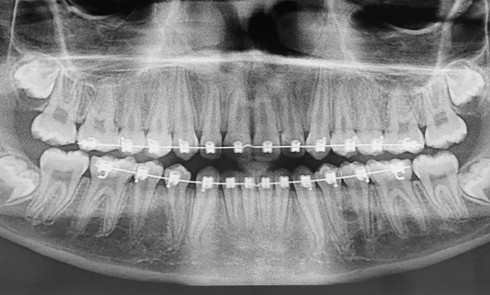

Contexte – Processus de décision La traction des lambeaux, nécessaire pour assurer la fermeture primaire des berges lors des procédures...